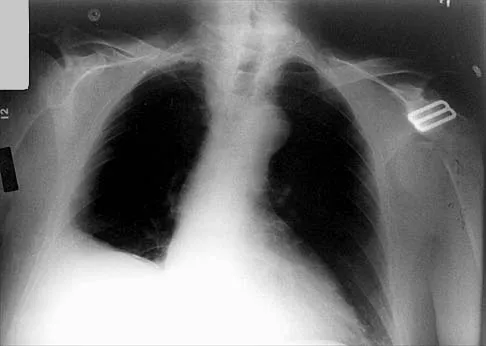

Question 95

Which of the following findings is seen in the chest radiograph shown in Figure 13?

Explanation